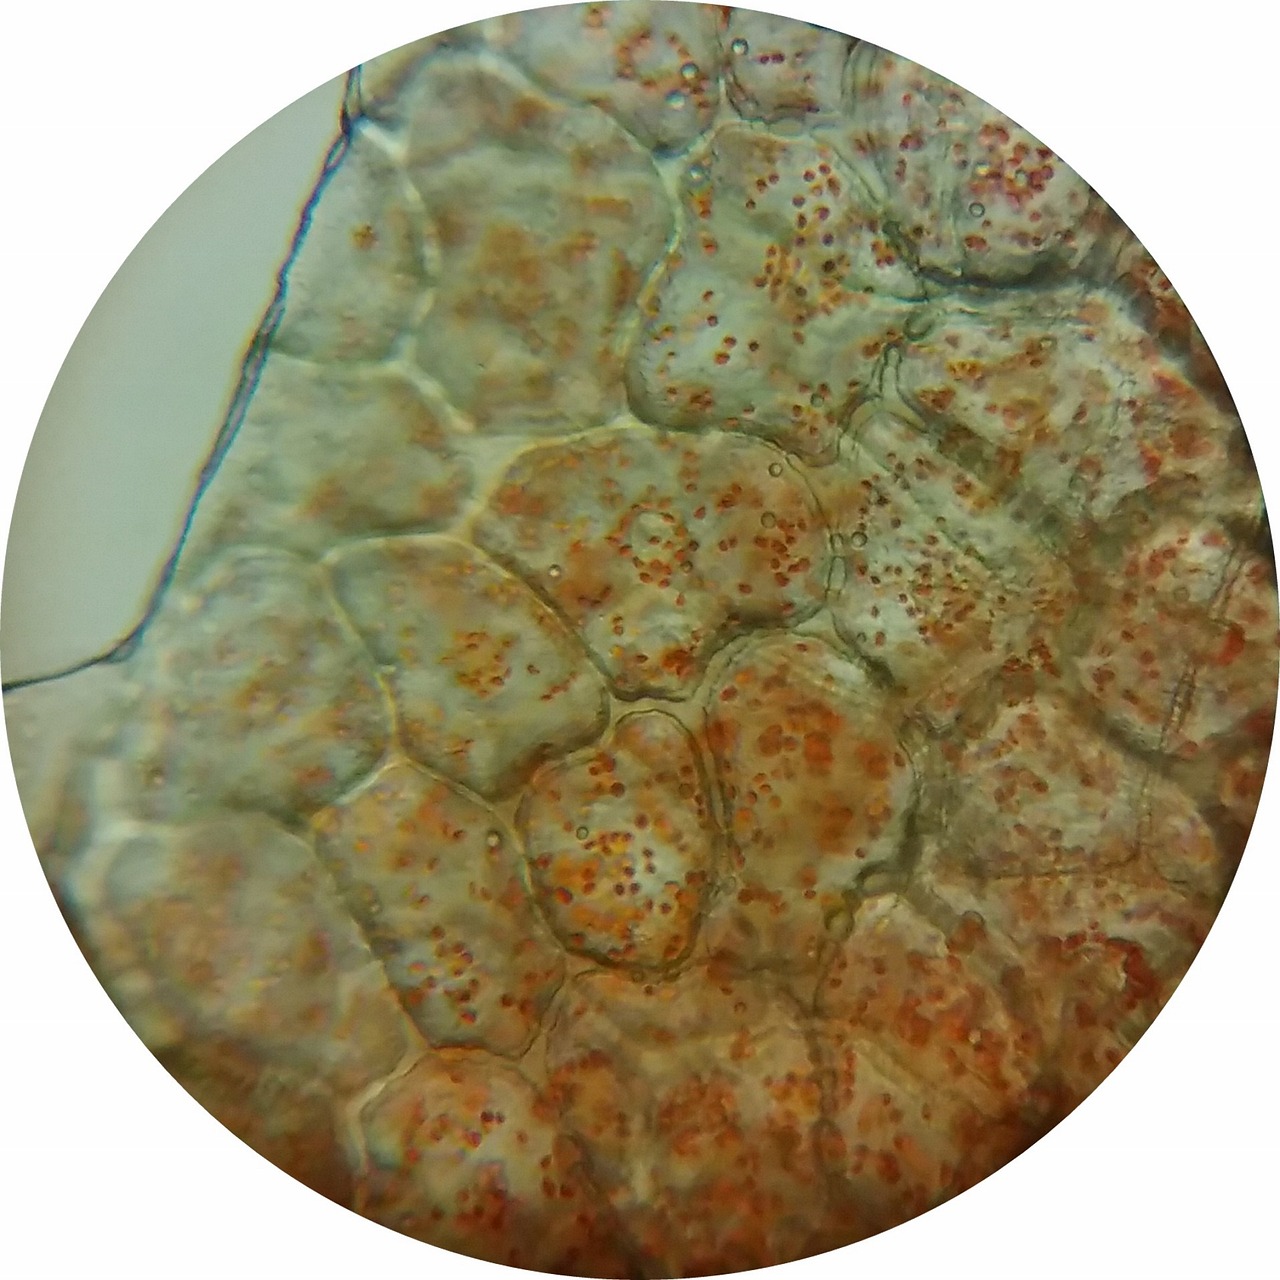

먼저 Chromogenic Immunohistochemistry(IHC)는 효소가 부착된 특정 항체(하나의 항체 또는 1차 및 2차 항체를 조합하여 사용)를 사용하여 조직 샘플에서 특정 항원의 분포 및 발현 정도를 측정하는 방법인데요,

항원 항체 반응이 일어나면 항체에 붙은 효소가 활성화 되고 그러면 이후 기질을 넣어주었을 때 효소가 기질과 반응해 발색성 침전물을 생성하기에 항원의 분포 및 위치를 확인1)할 수 있습니다.

참고로, IHC의 효소로 사용되는 Horeseradish peroxidase (HRP)은 기질(substrates)의 oxidation을 촉매하여 colored product를 생성하는데, 그 기질로 사용되는 것 중 DAB(3, 3'-diaminobenzidine)은 Brown에서 black 색깔을 띈다고 하고(near-neutral pH에 최적화),

Alkaline phosphatase(AP)는 substates로부터의 phosphate groups의 hydrolysis를 촉매하여, colored product를 생성하는데 , 기질로 사용되는 것 중 Fast Red는 빨간색을 띈다2)고 합니다(basic pH(pH 8~10)에서 최적화).

지금 읽고 있는 논문0)에서는 intestine section과 intestinal organoid의 세포들을 관찰하기 위해 IHC와 immunofluorescence를 모두 민감도가 우수한 indirect method 방식으로 사용했는데, IHC의 경우 horseradish peroxidase를 사용했고, 기질은 앞서 말한 brown 색을 띠는 DAB를 사용했습니다.

중요한건 IHC를 수행하기 위해서 endogenous peroxidase activity를 3% H2O2로 blocking했다고 하는데, endogenous peroxidase는 많은 세포에 자연적으로 존재하면서 HRP처럼 DAB라는 chromogen과 반응하여 염색을 유도할 수 있기에 정확한 염색 결과를 얻는데 방해할 수 있기에 비활성화시킨다5)고 합니다.

또한, 핵 염색을 위해서는 hematoxylin을 사용했는데, hematoxylin은 산화되면 aluminum ions와 결합하여 active metal-dye complex를 이루어 nuclear histones의 lysine residues에 결합하여 mammalian cells의 핵을 blue로 염색한다6)고 합니다.